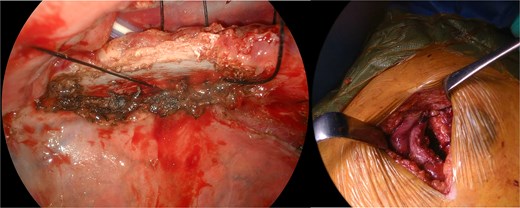

The patient underwent anterior thoracotomy at the site of the hernia, followed by scar resection of the previous incision. Additionally, a 12-mm port was placed at the sixth ICS to facilitate the observation of the thoracic cavity. The hernial defect was repaired exclusively with four stitches of size one nonabsorbable silk suture placed across the ICS between the fourth and fifth ribs, forming the hernial orifice (Fig. 3). Prior to suturing, the adhesion between the right upper lobe and fourth rib was meticulously dissected as extensively as possible. Resection of the herniated lung tissue was not required.

Intraoperative view of rib approximation using nonabsorbable sutures.